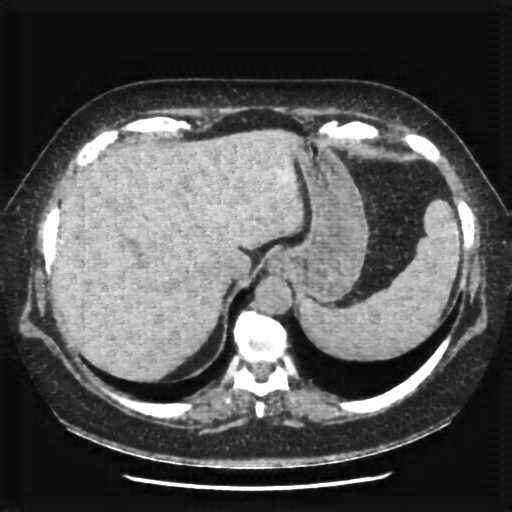

Image Grid

4×3 grid: Rows show different image types (Original NATIVE, Reconstructed NATIVE, Original VENOUS, Generated VENOUS), Columns show windowing techniques (No Window, Lung Window, Mediastinum Window)

Reconstructed NATIVE CT scan (cycle consistency)

Full window (WL 1023.5, WW 4095 → Low −1024, High +3071)

Actual HU range: [-798.0, 546.5]

Reconstructed NATIVE CT scan (cycle consistency)

Lung window (WL -600, WW 1500 → Low −1350, High +150)

Actual HU range: [-798.0, 150.0]

Generated VENOUS CT scan (A→B translation)

Generated VENOUS CT scan (A→B translation)

Lung window (WL -600, WW 1500 → Low −1350, High +150)

Actual HU range: [-783.9, 150.0]